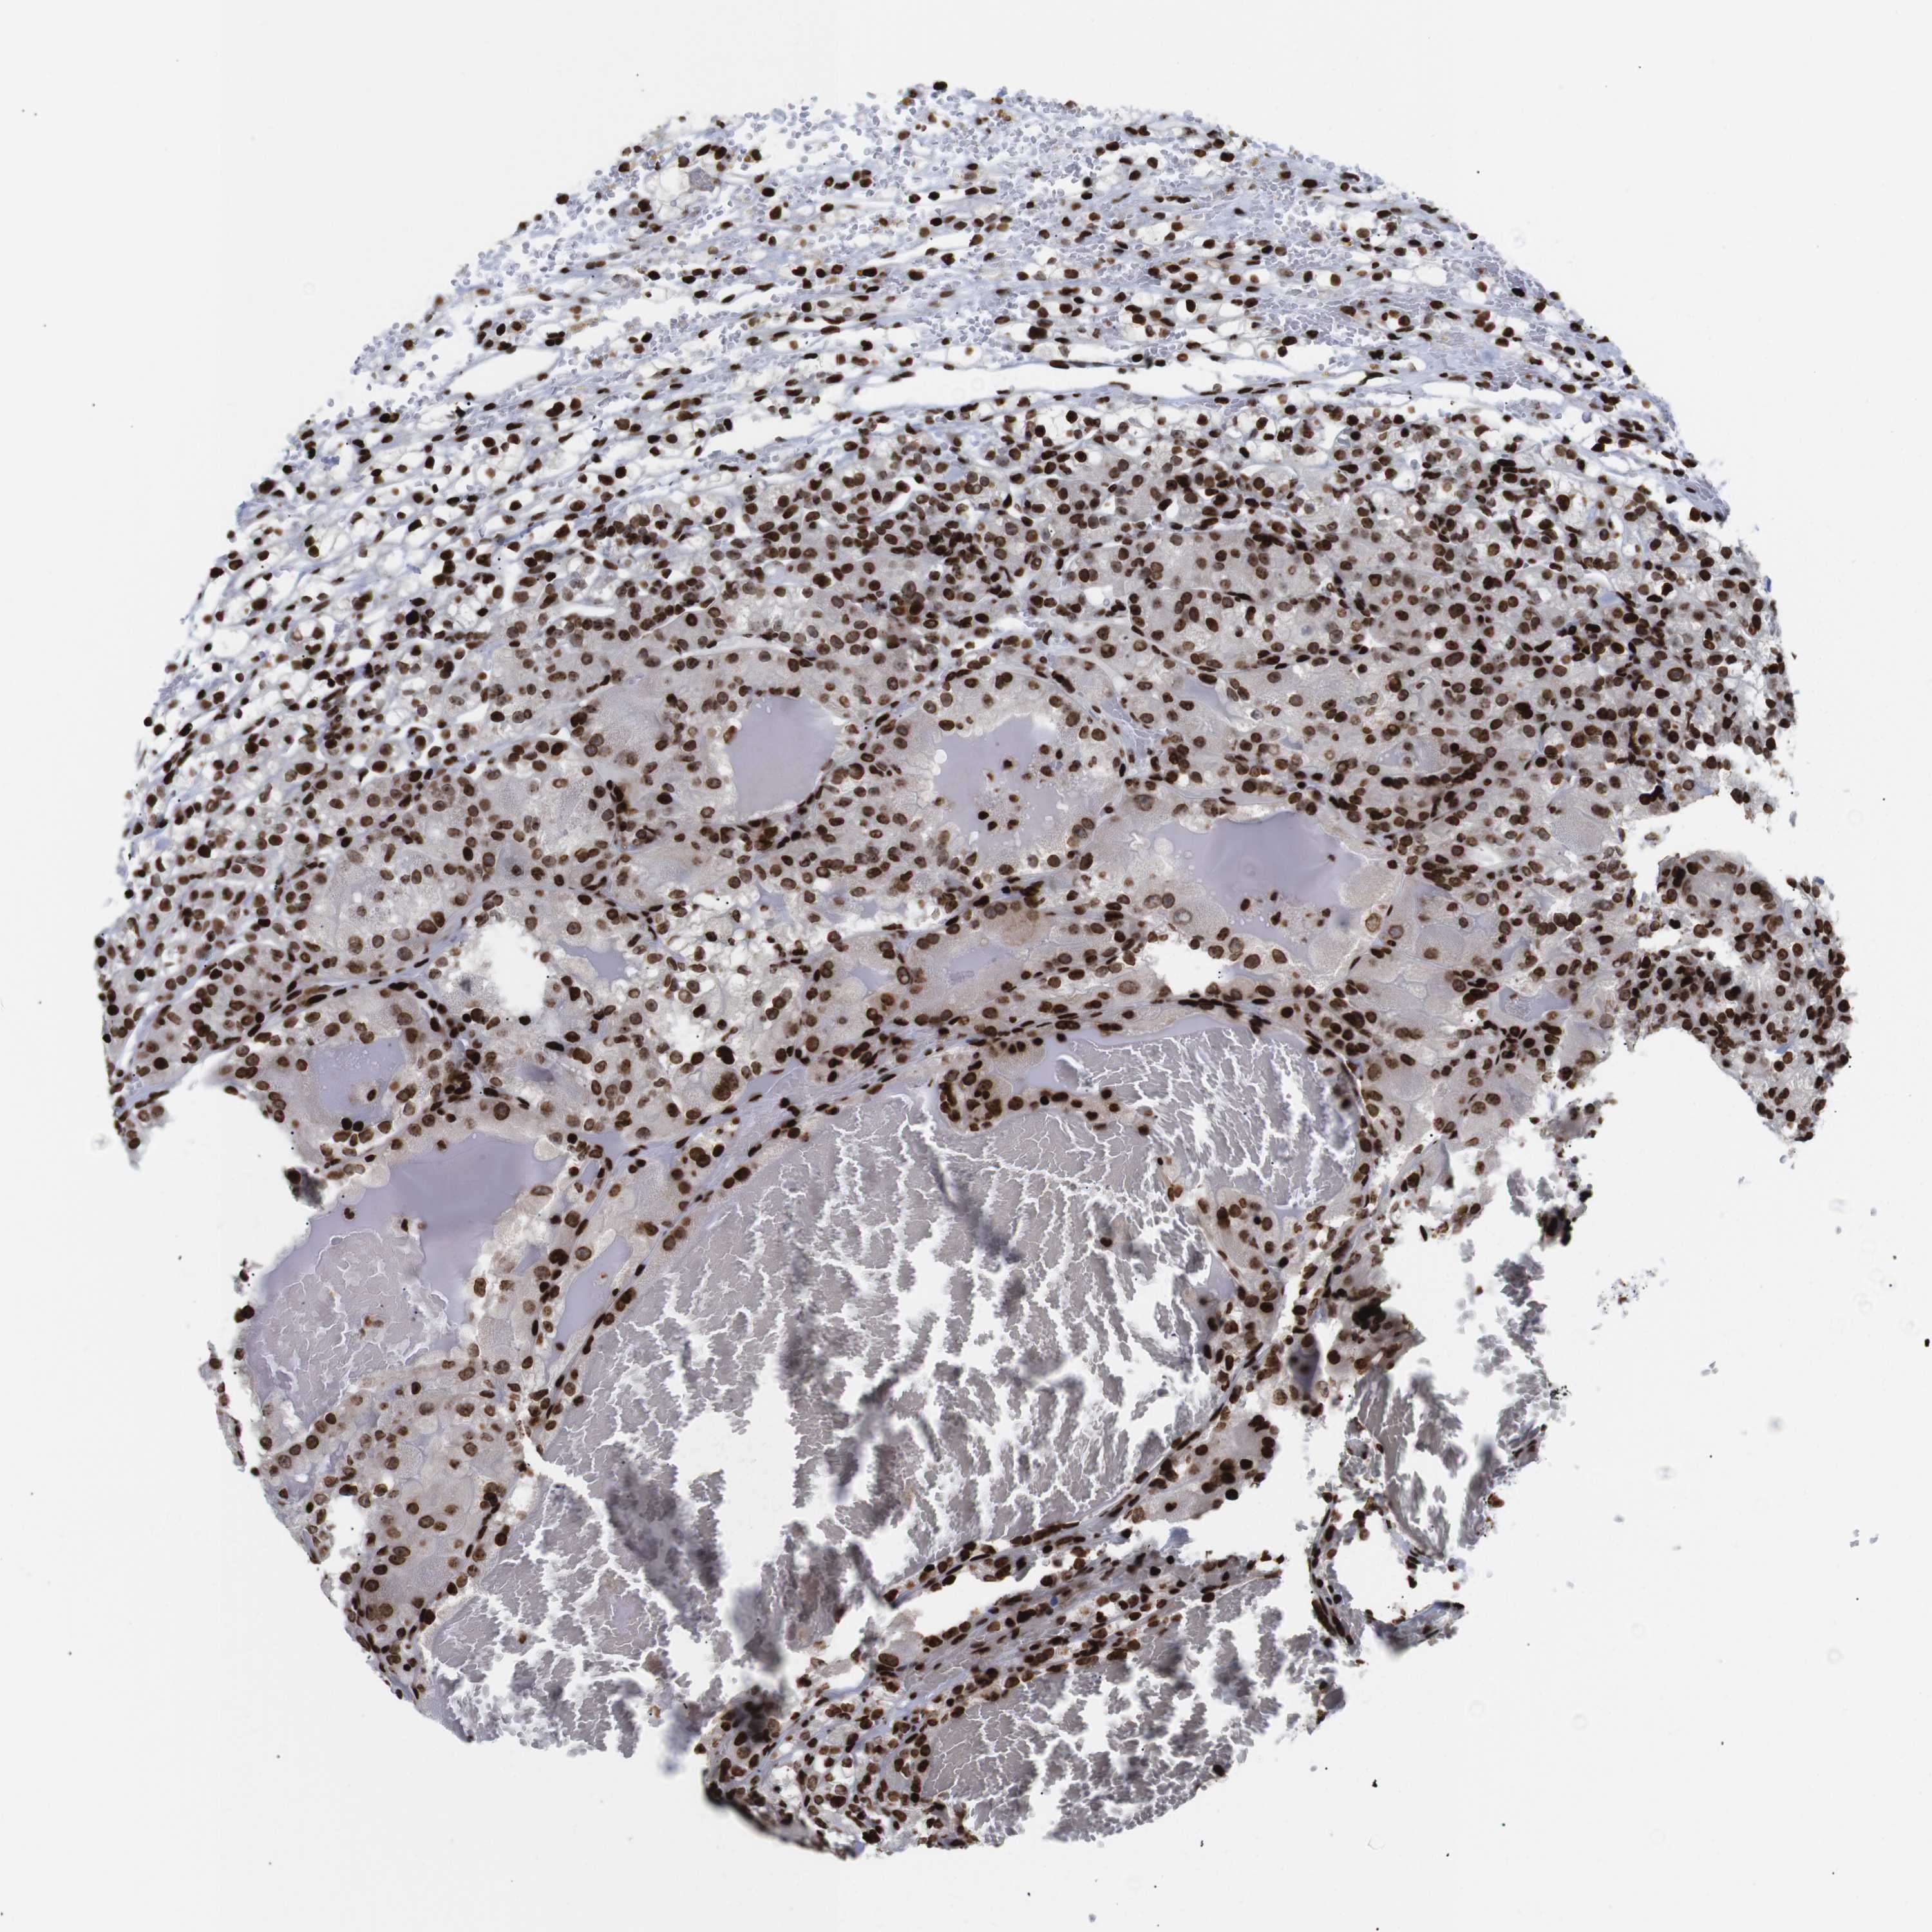

KIDNEY RENAL PAPILLARY CELL CARCINOMA (TCGA) - Interactive survival scatter ploti

The Survival Scatter plot shows the clinical status (i.e. dead or alive) for all individuals in the patient cohort, based on the same data that underlies the corresponding Kaplan-Meier plots. Patients that are alive at last time for follow-up are shown in blue and patients who have died during the study are shown in red.

The x-axis shows the expression levels (FPKM) of the investigated gene in the tumor tissue at the time of diagnosis. The y-axis shows the follow-up time after diagnosis (years). Both axes are complimented with kernel density curves demonstrating the data density over the axes. The top density plot shows the expression levels (FPKM) distribution among dead (red) and alive patients (blue). The right density plot shows the data density of the survived years of dead patients with high and low expression levels respectively, stratified using the cutoff indicated by the vertical dashed line through the Survival Scatter plot. This cutoff is automatically defined based on the FPKM cutoff that minimizes the p-score. The cutoff can be changed by dragging the vertical line or by entering a cutoff value in the square labeled "Current cut-off".

Under the Survival Scatter plot the p-score landscape (black curve; left axis) is shown together with dead median separation (red curve; right axis). Dead median separation is the difference in median mRNA expression between patients who have died with high and low expression, respectively. It is calculated as follows: median FPKM expression of dead patients with high expression - median FPKM expression of dead patients with low expression. This is intended to aid the user in visually exploring custom cutoffs and the associated p-scores and dead median separation.

Individual patient data is displayed and can be filtered by clicking on one or more of the category buttons on the top of the page. Categories describing expression level and patient information include: high, low, alive, dead, female, male and tumor stages. The scale of the x-axis can be toggled between linear and log-scale by clicking on the "x log" button. Mouse-over function shows TCGA ID, patient information and mRNA expression (FPKM) for each patient.

& Survival analysisi

Kaplan-Meier plots summarize results from analysis of correlation between mRNA expression level and patient survival. Patients were divided based on level of expression into one of the two groups "low" (under cut off) or "high" (over cut off). X-axis shows time for survival (years) and y-axis shows the probability of survival, where 1.0 corresponds to 100 percent.

H1-4 is not prognostic in Kidney Renal Papillary Cell Carcinoma (TCGA)